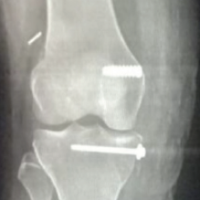

Figure 1: A 33-year-old male with secondary osteoarthritis of the right hip due to osteonecrosis of the femoral head. Sequential radiographic and clinical images demonstrate stable press-fit acetabular cup fixation without screws and progressive recovery with early weight bearing. (a) Pre-operative radiograph showing secondary osteoarthritis changes with a deformed head due to osteonecrosis of the femoral head. (b) Immediate post-operative radiograph showing a well-seated press-fit cup in optimal position. (c) Three-month post-operative radiograph showing maintained cup alignment. (d) Twelve-month follow-up radiograph confirming osseointegration and stable fixation. (e, f, g) Clinical photographs at 12 months demonstrating pain-free hip flexion, abduction, and adduction.